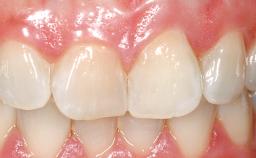

Immediate Flapless Placement of an Implant in a Maxillary Left Central Incisor Site

A 42-year-old female patient was referred to our clinic at the School of Dentistry of the University of São Paulo in November 2004, presenting a deficient restoration in the upper left central incisor. The clinical examination revealed no gingival retraction or any signs of gingival inflammation and, therefore, previous periodontal treatment was not considered. The patient presented a high lip line at full smile and a thin tissue biotype. This combination characterized a high-risk situation from an anatomic point of view, which required careful preoperative planning and cautious surgical execution.

Soft Tissue Contour and Volume Ideal